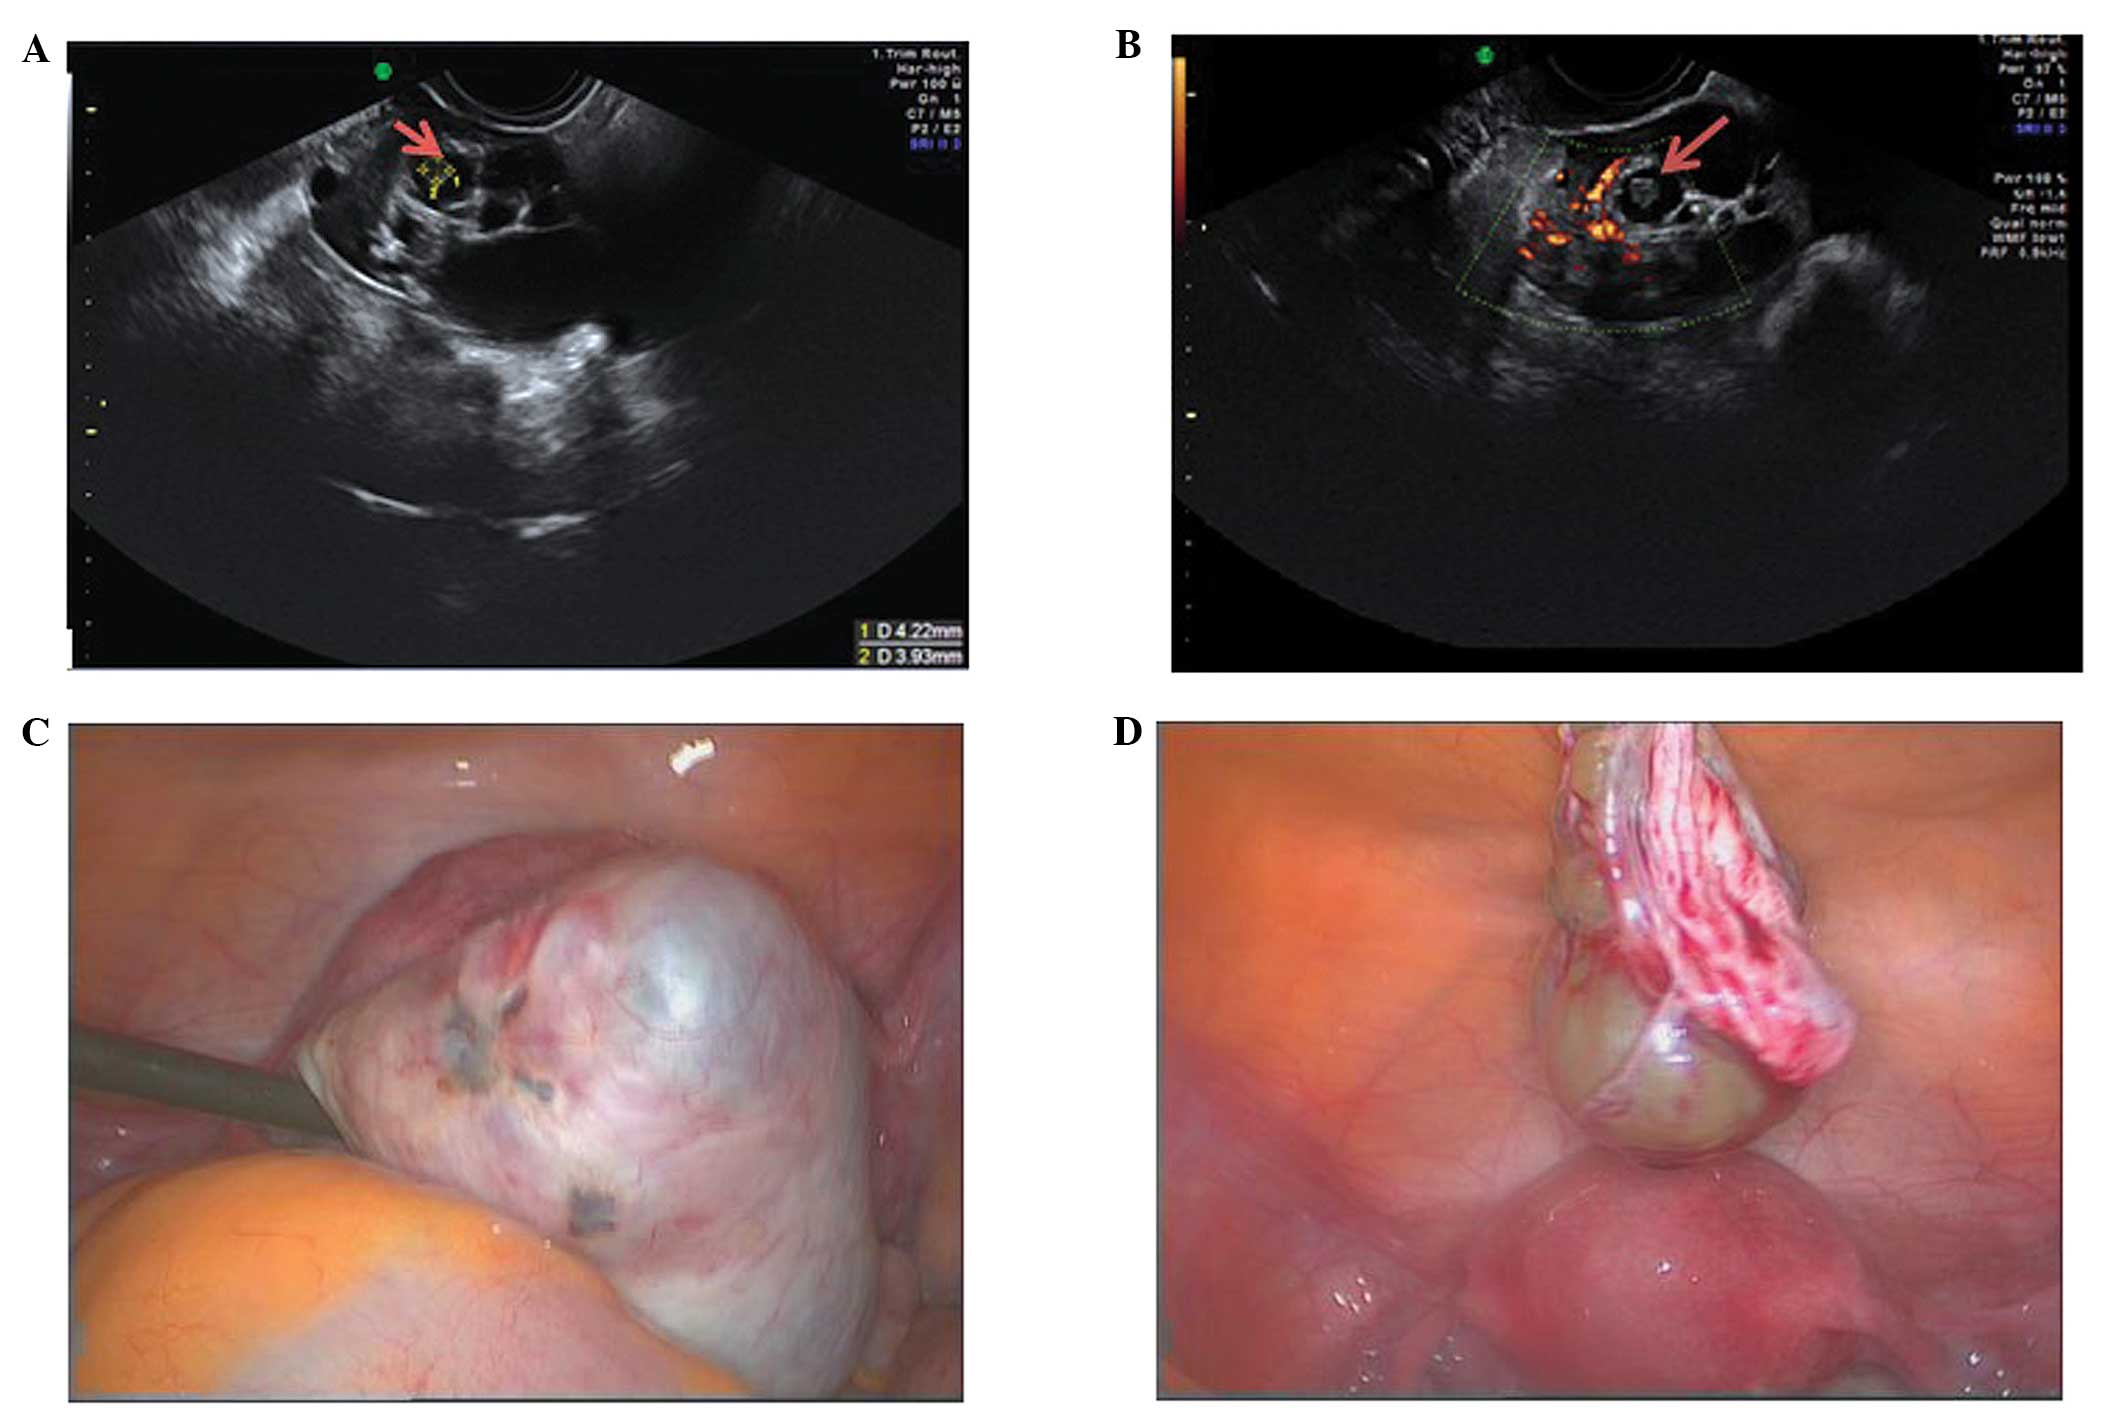

Ovarian stromal tumors (struma ovarii)

Struma ovarii is a rare subtype of mature teratoma characterized by the presence of ectopic thyroid tissue. They account for <5% of mature teratomas (38). Although a preoperative diagnosis is not always possible, they have been described as having a similar appearances to mature teratomas but with increased vascularity in the central part of the mass (39). They are difficult to classify (40), but are of interest morphologically because they have been associated with a sonographic sign called the ‘struma pearl’. These are rounded hyperechogenic structures with smooth surfaces, with increased vascularity on Doppler examination (40) (Fig. 20).

Figure 20

Struma ovarii showing (A) multilocularity and struma pearl formation (arrow) as well as (B) central vascularity (arrow pointing toward the ‘pearl’). (C and D) Laparoscopic features of the same cyst at the time of cystectomy.